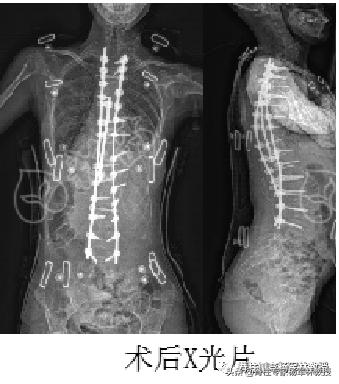

在今年5月21号,迎来了决战时刻,经过7个多小时,杨教授与带领的团队完胜了敌人,我也一夜之间长高了9厘米。

从那一刻起,我再也不用担心压迫心肺而心肺衰竭,再也不用担心压迫神经而下肢瘫痪,再也不用担心脊柱侧弯而被嘲笑!

术后半年复诊,恢复良好